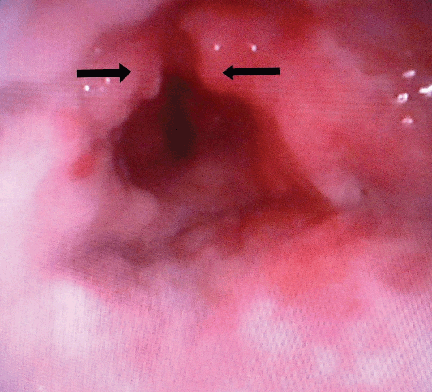

On local examination, indirect laryngoscopic examination showed a growth involving the supraglottis. There were no palpable lymph nodes in the neck. Examination of the ears and nose with para nasal sinuses (PNS) did not reveal any abnormality. In the routine examination of blood, hemoglobin estimation was 8.7 g/dL, erythrocyte sedimentation rate of 15 mm was seen at the end of first hour (AEFH). Total leucocyte count of 8600 per high powered field and differential leukocyte count of neutrophils 60%, lymphocytes 30%, monocyte 8% and eosinophil count of 2% was seen. Liver function tests were normal. Chest X-ray posterior anterior view showed normal lung fields. Direct fiberoptic laryngoscopy examination showed a polypoidal growth with hyperemia involving the epiglottis and bilateral aryepiglottic folds. (Figure 1) Bilateral vocal cord mobility was normal. Multiple punch biopsies were taken from the polypoidal growth. Ultrasonography of the abdomen did not reveal any findings suggestive of abdominal tubercular lesion. Serological test for human immunodeficiency virus was non reactive. The histopathological examination showed features of necrotizing inflammatory infiltrate lined by hyperplastic squamous epithelium and epithelioid granuloma with Langhan’s giant cells. (Figure 2A–B) Ziehl–Neelsen staining on the tissue section showed the presence of scanty acid-fast bacilli. Fiberoptic bronchoscopy was done for collection of bronchioalveolar lavage (BAL) fluid and examination for acid-fast bacilli. On microscopic examination of the bronchioalveolar lavage fluid, acid-fast bacilli were not seen by Ziehl–Neelsen staining. The diagnosis of primary laryngeal tuberculosis was confirmed. The patient was treated with anti-tubercular therapy for six months.

Cursor on image to zoom/Click text to open image

Figure 1: Direct laryngoscopic picture showing growth involving supraglottic larynx with arrows pointing at polypoidal lesion.